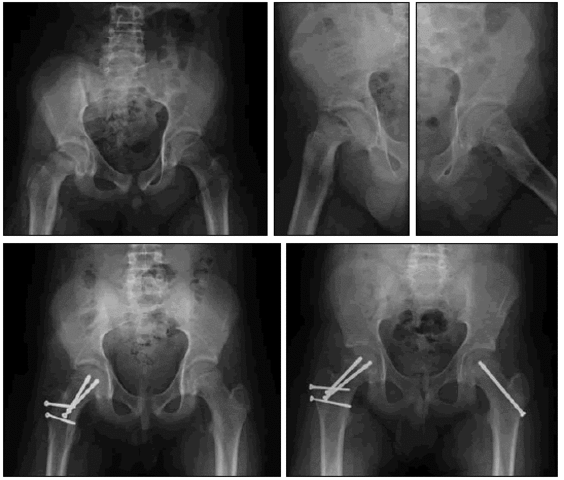

My first surgery

After discovering the dislocation , the doctors had to have surgery a few days later

My second surgery

Something went wrong with the surgery and had to have surgery again.